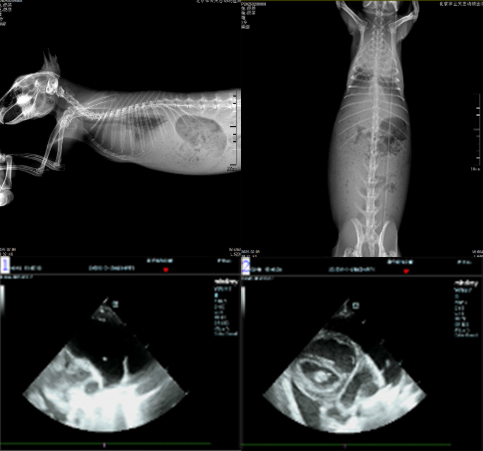

★病例名称:垂耳兔心脏病

1、患宠品种:垂耳兔

2、患宠名字:奶茶

3、患宠年龄:3岁6个月

4、患宠性别:雄

5、体格检查:就诊前一天突然觉得呼吸困难,腹式呼吸。就诊当天精神食欲不佳、大便颗粒小、鼻孔张开幅度大,听诊心音弱、心率慢。

6、难点描述:患宠呼吸困难,有胸腔积液,且应激,治疗操作风险较高。

7、诊断过程:体格检查后进行DR、血检、心脏超声、CT等检查,确诊兔子患心脏病。

8、治疗方法:经与主人沟通后,放置胸导管排出胸腔积液,安排口服用药,入住ICU实时监测。

9、预后情况:经过悉心治疗,患宠胸腔积液恢复,呼吸、饮食、精神恢复,为巩固治疗效果需要继续口服药治疗。